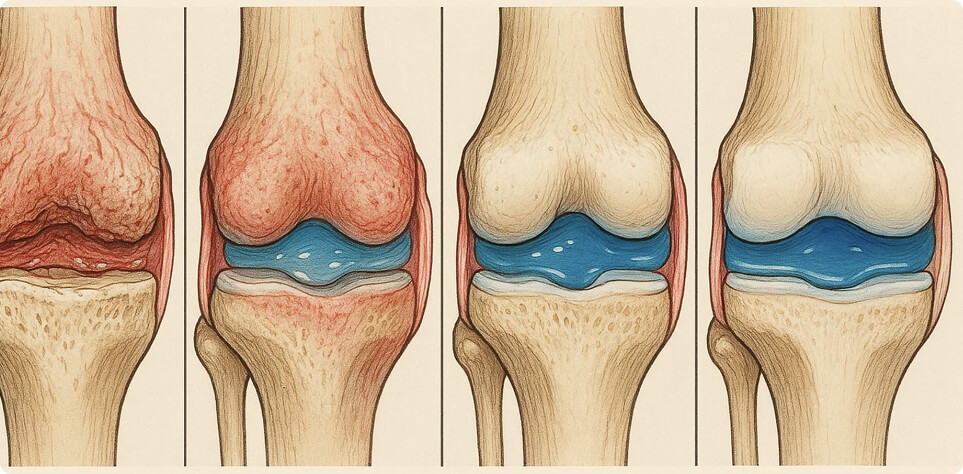

Usura irreversibile della cartilagine, causando dolore intenso e rigidità permanente.

Il dolore al ginocchio non nasce dal nulla — è causato da usura silenziosa, infiammazione e deterioramento delle articolazioni. Flexosamine agisce direttamente alla radice del problema. I suoi ingredienti attivi penetrano profondamente nella membrana articolare, combattendo l’infiammazione e rigenerando la cartilagine danneggiata.

- Allevia anche i dolori articolari più forti. Restituisce la comodità del movimento. Ripristina la normale circolazione sanguigna, riduce il gonfiore.

- Allevia l’infiammazione, impedendo il danneggiamento dell’articolazione e prevenendo danni irreversibili. Avvia il processo di recupero delle articolazioni.

- l’articolazione riacquista la sua mobilità e tutte le sue funzioni. L’articolazione è resistente e non dolorante anche sotto sfress (freddo, cambiamento di clima, sforzo).